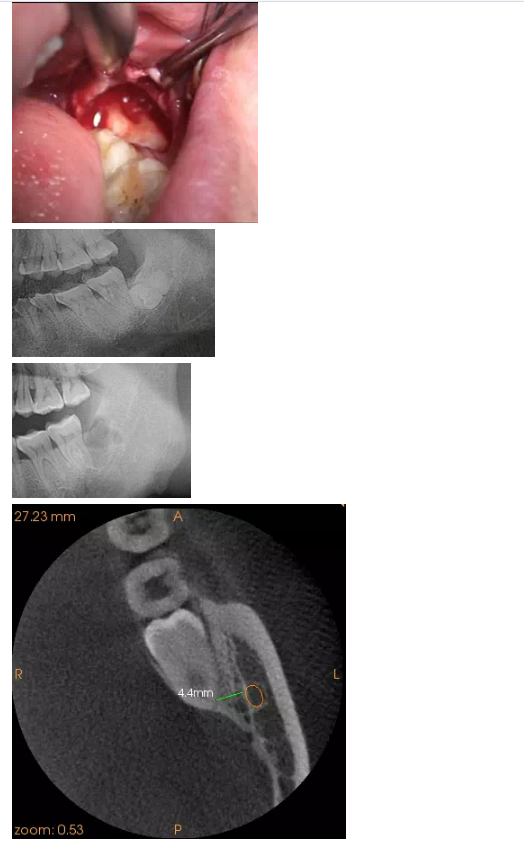

一位患者要求拔左側(cè)智齒,全景片顯示:根尖三分之一處于下牙槽神經(jīng)管重疊,CT顯示整顆牙都位于下牙槽神經(jīng)管的舌側(cè),最近的距離位為4.4mm,這給整個(gè)術(shù)前診斷起了決定性的作用。